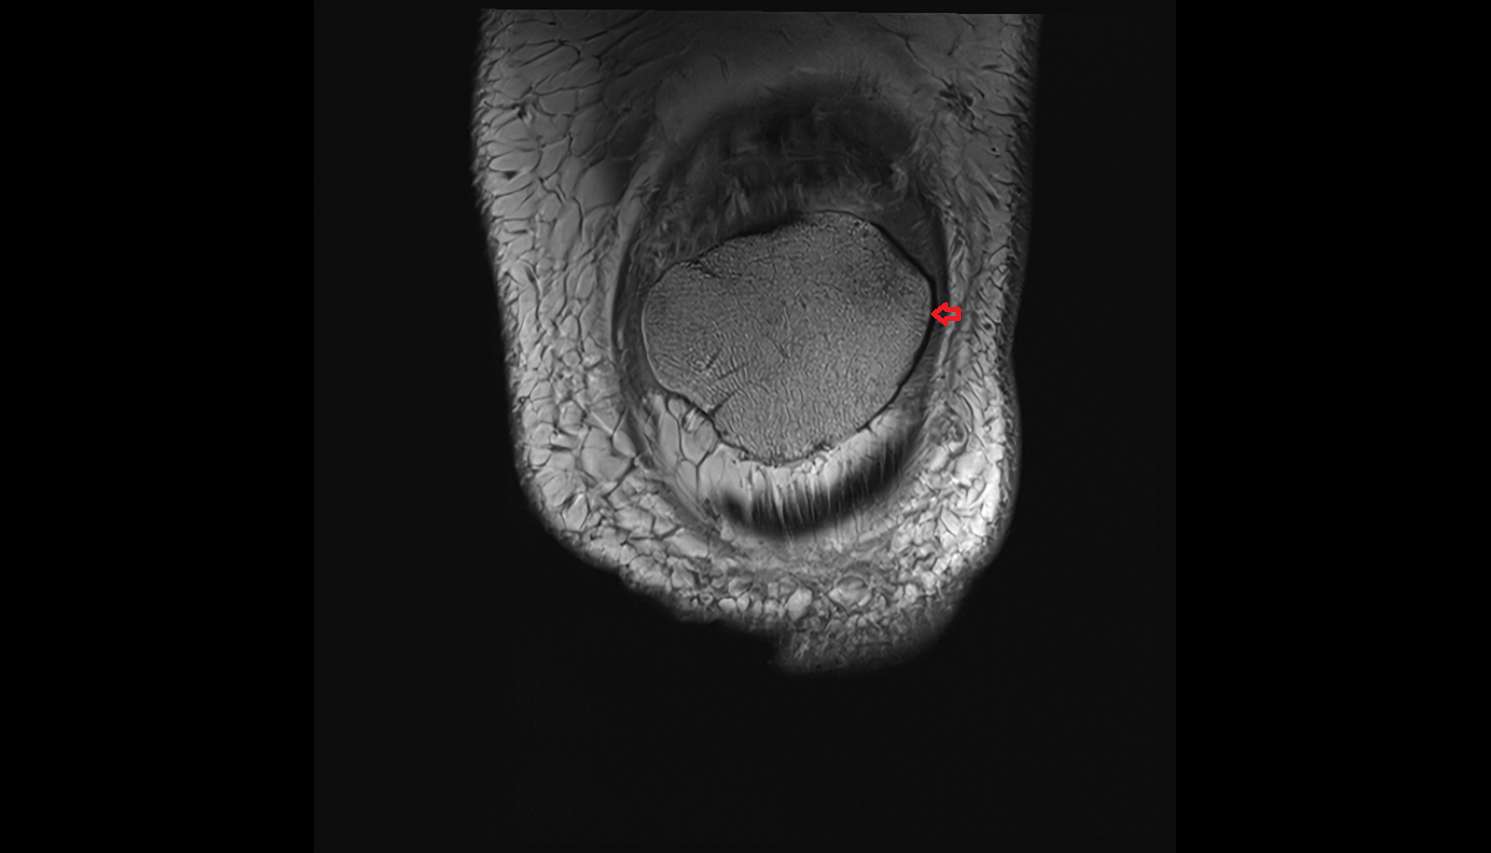

- Patella

- Patellar articular cartilage

- Medial articular facet of patella

- Lateral articular facet of patella